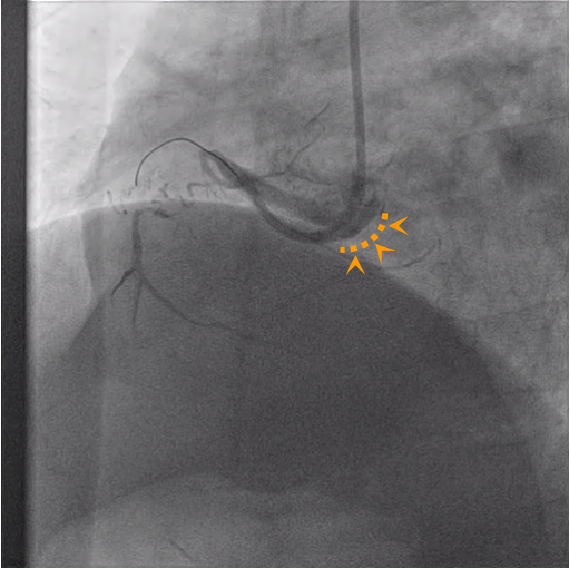

右冠分叉病变:右冠状动脉扭曲较严重,近中段以及远段至后降支近段存在重度狭窄。

此患者为分叉病变,罪犯血管是右冠状动脉远段至后降支近段;

此病变类型为真性分叉病变;

右冠状动脉全程较为迂曲伴钙化,可能会为随后器械推送带来阻力和困难;

双导丝分别到达后降支和左室后支远端,并进行球囊扩张。

右冠状动脉远段至后降支近段植入一枚支架,左室后支近段药物球囊扩张,最后欧进行对吻扩张,近中段FFR值在正常范围,未予以干预。